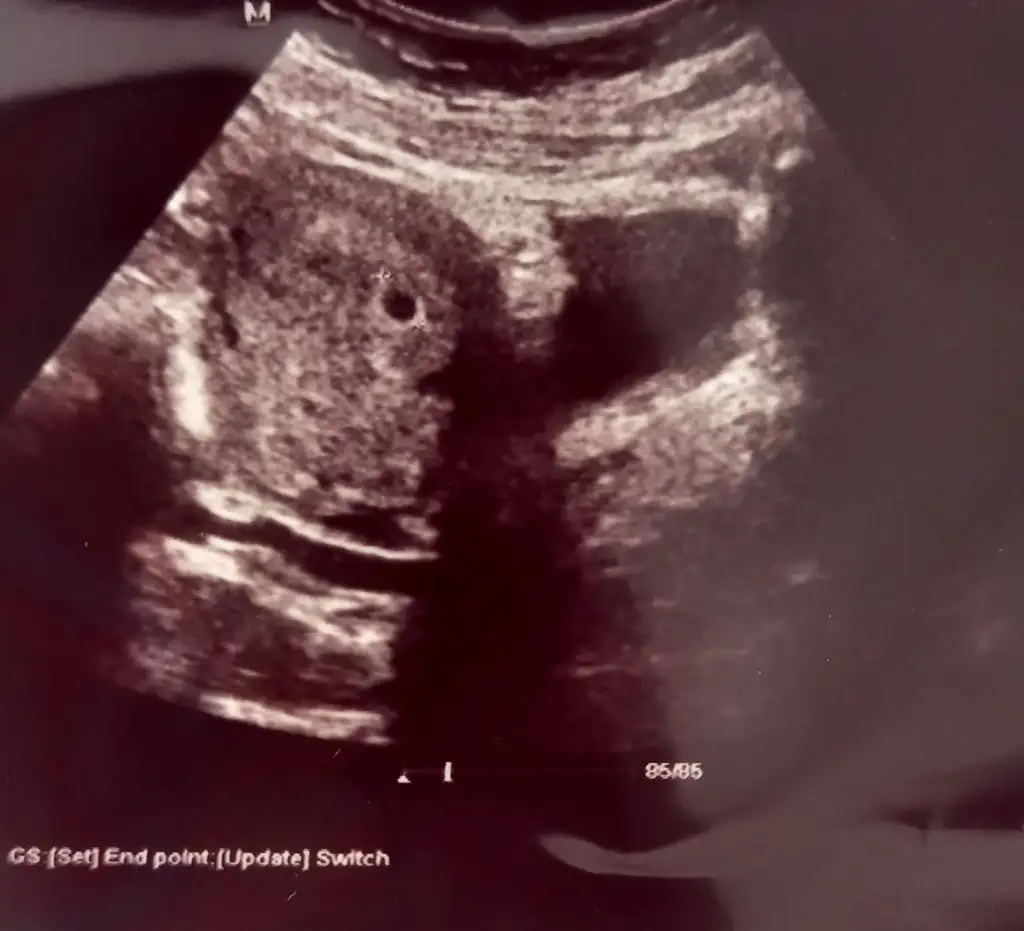

Maşallah Bana alttan baktı yolk kesesi bile azıcık görünüyordu beyaz beyaz baya netti kese . Özele gittim, cihazı da baya iyiydi . Çok şükür. 2 hafta sonra gel kalp atışı için dedi yani 7.haftaya denk geliyor

Maşallah kaçıncı haftadasınız bana 6.hafta herhangi bir gün gel kalp atışına bakalım dedi